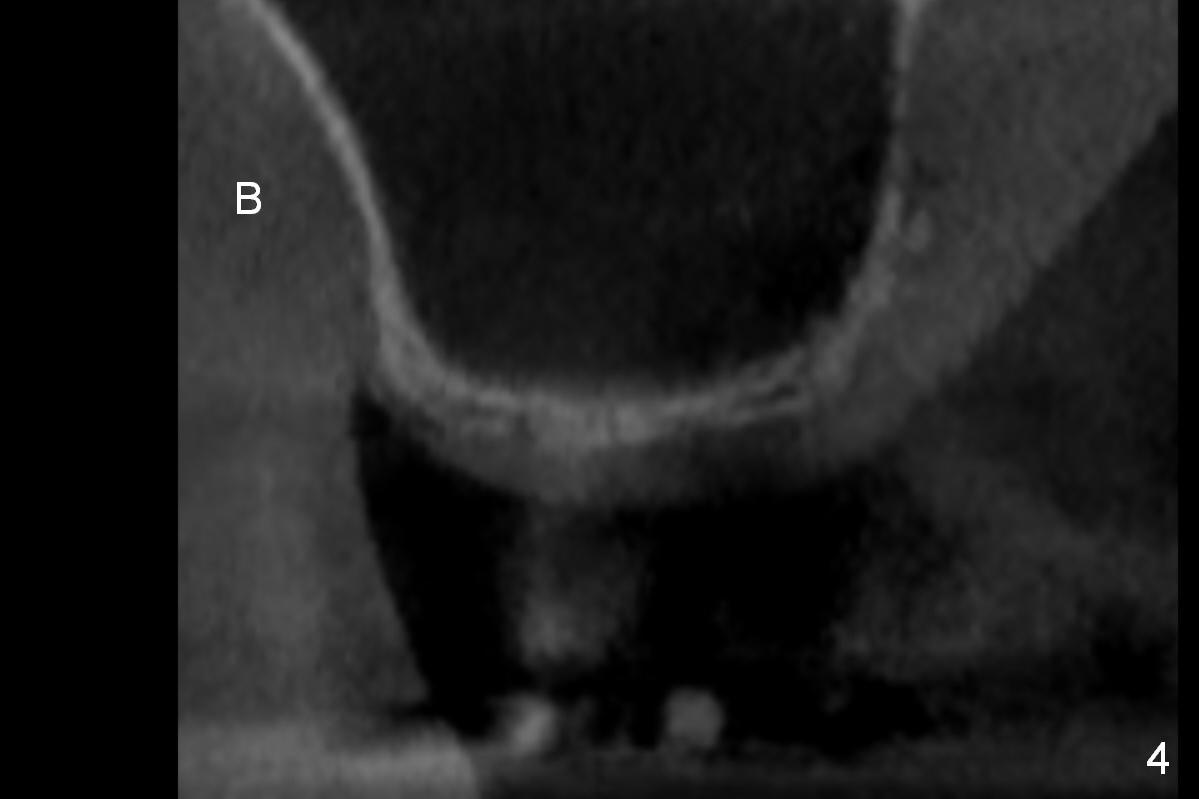

A 78-year-old man needs implant restoration at #2 in spite of limited bone height, because of severe ridge atrophy at #18 and 19. Sagittal (Fig.1-3) and coronal (Fig.4-6) sections show bone height less than 1 mm. If there is plenty of the keratinized tissue at #2, use a 4 mm tissue punch for access, followed by sinus lifter. Use fine and coarse allograft for sinus lift.